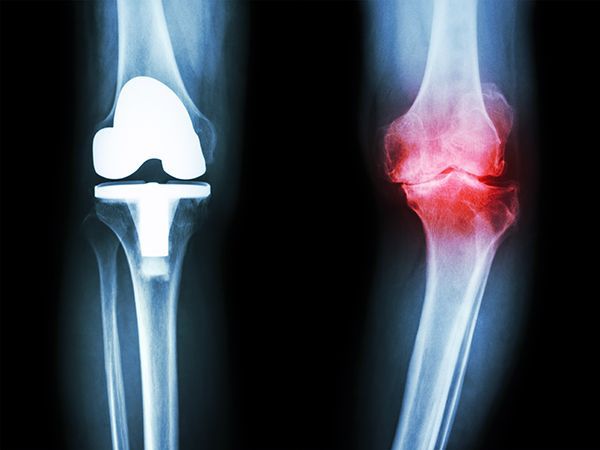

Arthritis and degenerative joint conditions are among the most common causes of chronic pain, stiffness, and reduced mobility. These conditions develop over time as the cartilage within joints wears down, leading to inflammation and discomfort that can affect daily activities.

Degenerative joint conditions refer to disorders that cause gradual breakdown of cartilage and joint structures over time. As the protective cartilage wears away, bones may rub against each other, leading to pain, swelling, and stiffness.

Symptoms of Arthritis & Joint Degeneration

Symptoms may develop gradually and worsen over time.

Common signs include:

- Joint pain and tenderness

- Stiffness, especially in the morning

- Swelling or inflammation

- Reduced range of motion

- Weakness or instability

- Pain that worsens with activity